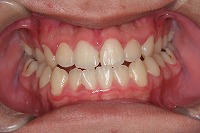

正面

反対咬合と下顎が出ている事を主訴に来院された、初診時18歳1か月の男性です。診断「上顎骨の後方位による骨格性反対咬合」非抜歯での矯正治療と、下顎を後退させる外科手術を併用して治療を行いました。